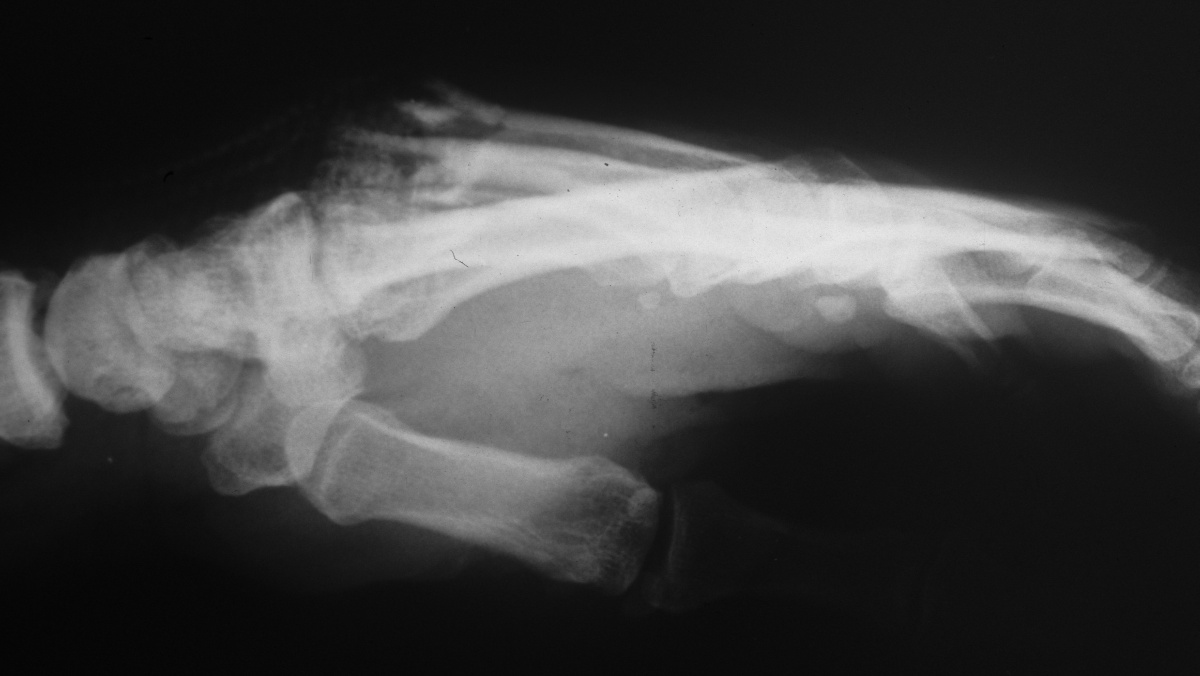

| Middle and ring

metacarpal base fractures with pulverized middle

metacarpal base. |